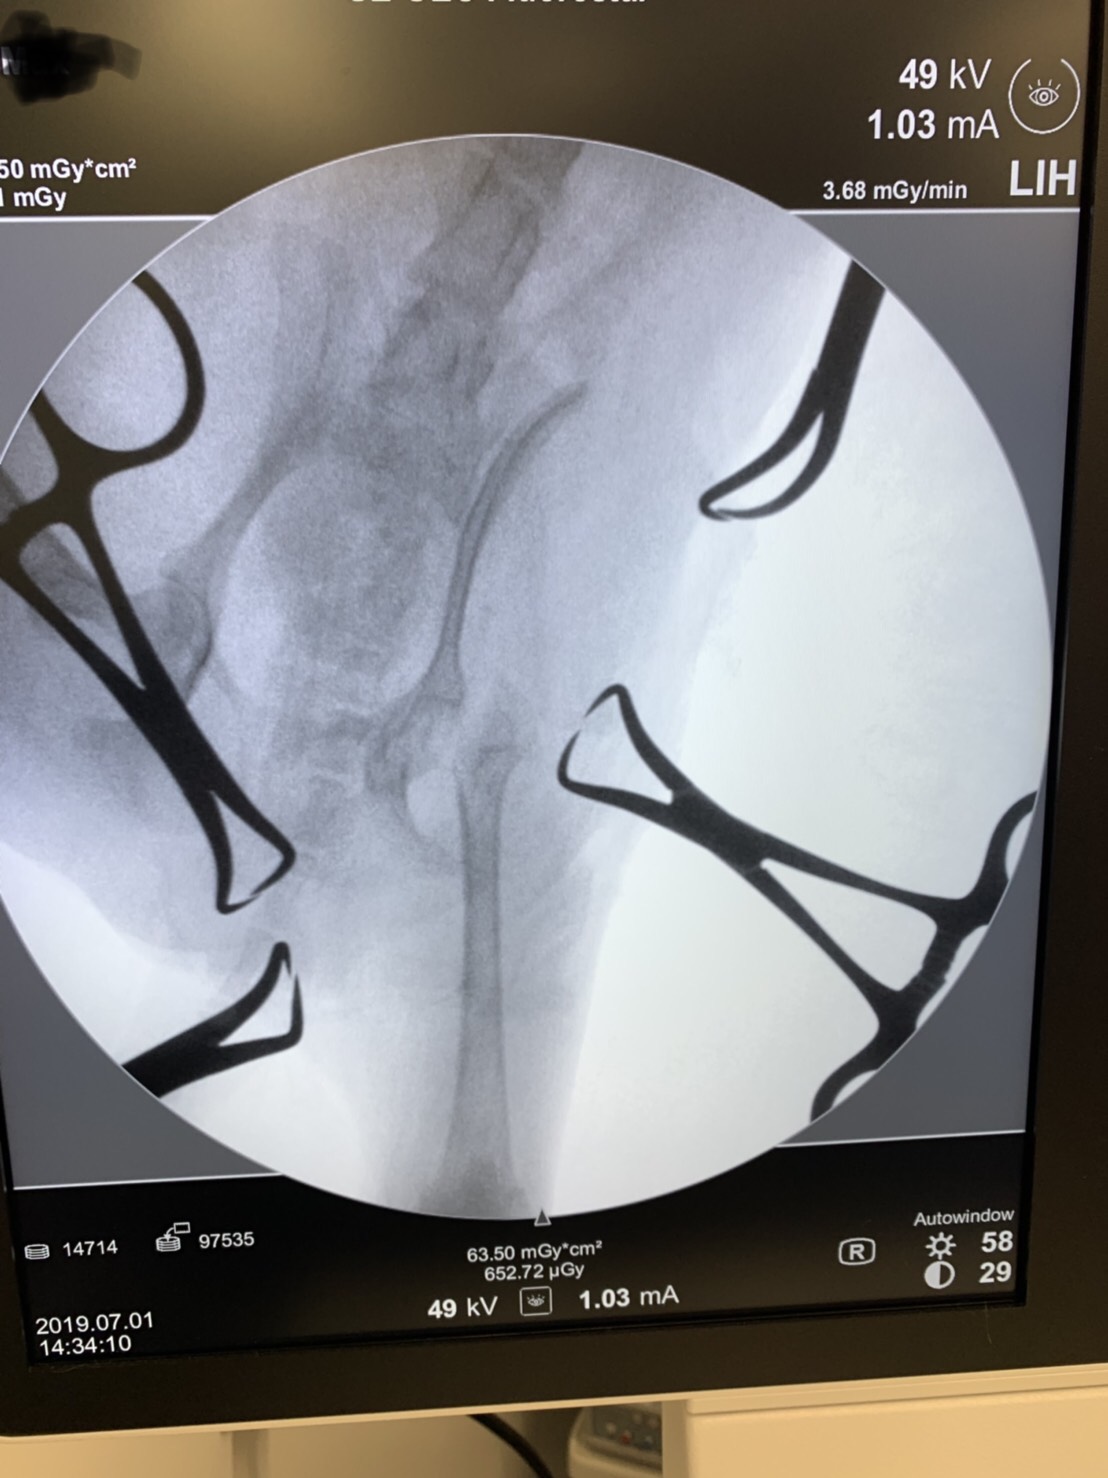

術中、骨頭・骨頚部切除後。Cアームという特殊なX線装置を使い、切除ラインが適切かどうかを確認します